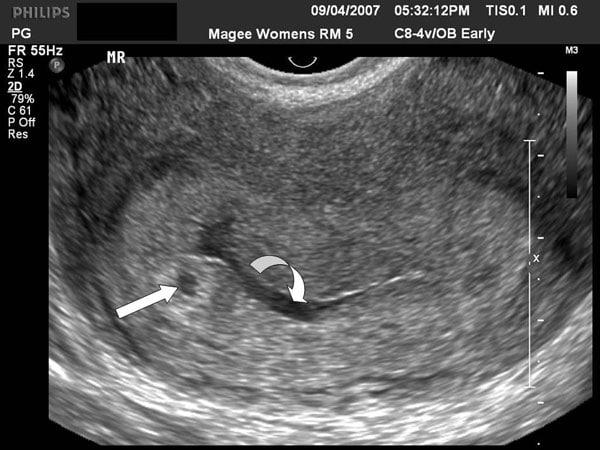

This comprehensive course covers the transvaginal evaluation of early pregnancy, focusing on normal and abnormal findings in the 1st trimester. Learn how to assess implantation, the development of the gestational sac, and the yolk sac, along with key sonographic markers for early pregnancy complications. Explore the role of Doppler studies in detecting abnormal placental development, and gain insights into the management of conditions like threatened miscarriage, hydatidiform mole, and embryonic demise. Perfect for healthcare professionals looking to enhance their skills in early pregnancy ultrasound.

Advanced Ultrasound Techniques: Uterine Artery Doppler First Trimester Pre-Eclampsia Screening